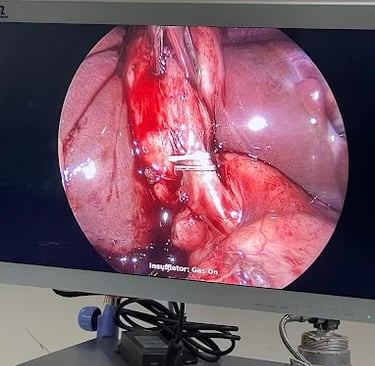

Laparoscopic surgery

Removal of Ovarian cyst

Gall Bladder removal by Lap